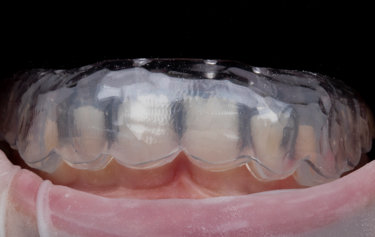

Figure 7: Indirect orthodontic bracket bond-up stents in-situ

The full restoration of all the patient’s upper and lower teeth was completed using this process at the same visit in only 2 hours. We were able to immediately then place upper and lower orthodontic brackets using an in-direct set-up technique through CFast orthodontics. This stent-guided application method means a much quicker and simpler fixation of the bracket to the teeth. Due to the incredible accuracy of the SmileFast stent, the composite restorations placed are a perfect replication of the digital model on which the orthodontic set-up was manufactured, therefore the stent for the orthodontics was a perfect fit, as shown in Figure 7. Within 4 hours all the patient’s teeth were fully restored and the fixed orthodontics applied and activated with 0.014 NiTi wires (Fig. 8). After 5-months the teeth were aligned into a more favourable position and the passive over-eruption of the teeth had been reversed (Fig.9). The patient was comfortable and occlusion functioning well, so it was decided to move forward with the second phase of her rehabilitation, the planning and provision of her final ceramics.